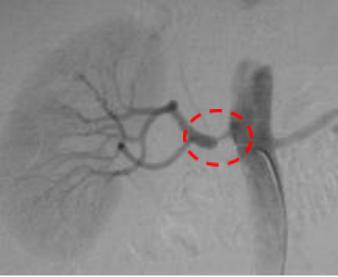

下肢动脉硬化闭塞症导致的右侧髂动脉闭塞,行走后右腿乏力,足部凉伴有疼痛破溃。造影提示右侧髂动脉重度狭窄,血流通过受限。

治疗前